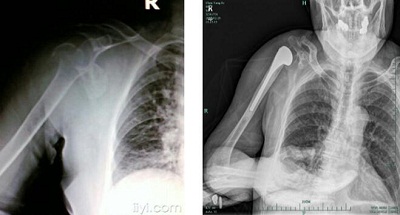

2017年2月6日,我院骨科陈昌伟主任团队成功地为一位陈旧性肱骨头和肱骨外科颈粉碎性骨折的高龄患者实施了半肩关节置换手术。

患者男,86岁,因跌倒致右肩关节疼痛活动障碍3月余入院。患者1个多月前在家中不慎摔倒致右肱骨头和外科颈粉碎性骨折、肱骨头严重移位。由于高龄体弱,合并”三高症”、脑梗塞后遗症、肺气肿等多种基础疾病,被多家医院拒绝手术。在家中休息了3个多月,患者感觉右肩活动障碍、疼痛加重,穿衣、吃饭无法自理,严重影响日常生活。新年伊始,患者慕名来到我院骨科就诊,骨科陈昌伟主任医师对病人进行了详尽的术前检查和评估,请心血管科、神经内科、呼吸科、麻醉科等相关科室会诊治疗,和患者家属就治疗方案进行了详细沟通,最后成功为患者实施了半肩关节置换术。手术顺利,耗时仅1小时。术后患者疼痛好转,右肩功能明显改善,吃饭、穿衣可以自行解决,病人和家属非常满意,现已顺利拆线出院。